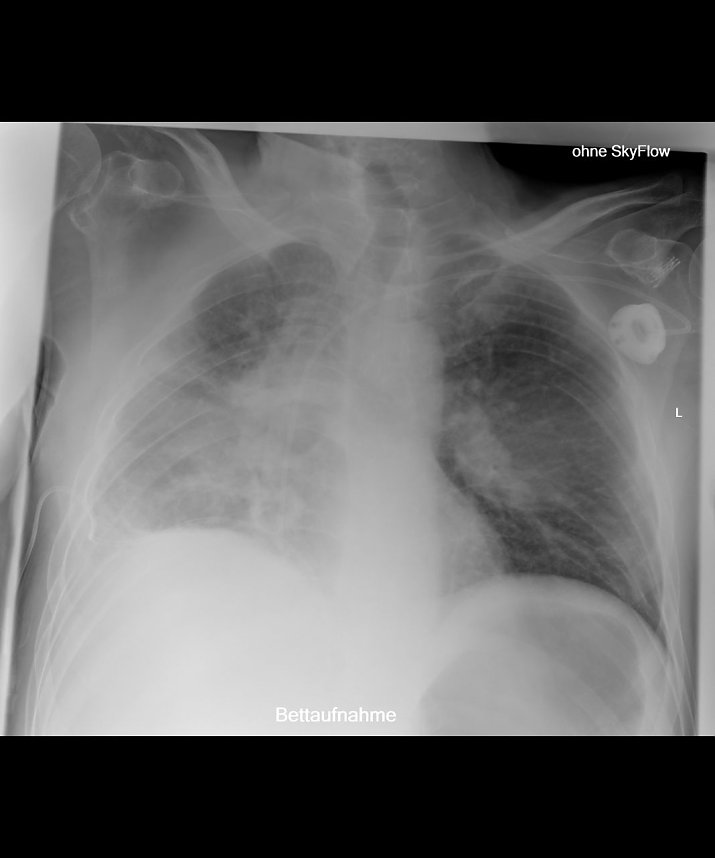

Liegendaufnahme zunächst ohne SkyFlow Technologie (Foto: red)